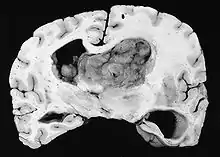

| GFAP stained microscopic section of a subependymal giant cell astrocytoma | |